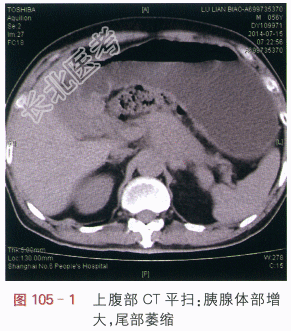

影像学资料如图105-1~图105-4所示。

读片分析:上腹部CT平扫显示胰腺体部增大,密度均匀,尾部萎缩,胰腺周边模糊(见图105-1),增强扫描动脉期:胰腺体部不规则肿块,增强后动脉期呈低密度,肿块边缘不清,肿块包绕脾动脉、腹腔干动脉(见图105-2);门脉期:胰腺体部不规则低密度肿块,肿块包绕脾静脉(见图105-3)。延时期肿块密度呈低密度,肿块包绕腹腔血管、并向周边侵犯,左肾上腺体积增大(见图105-4)。